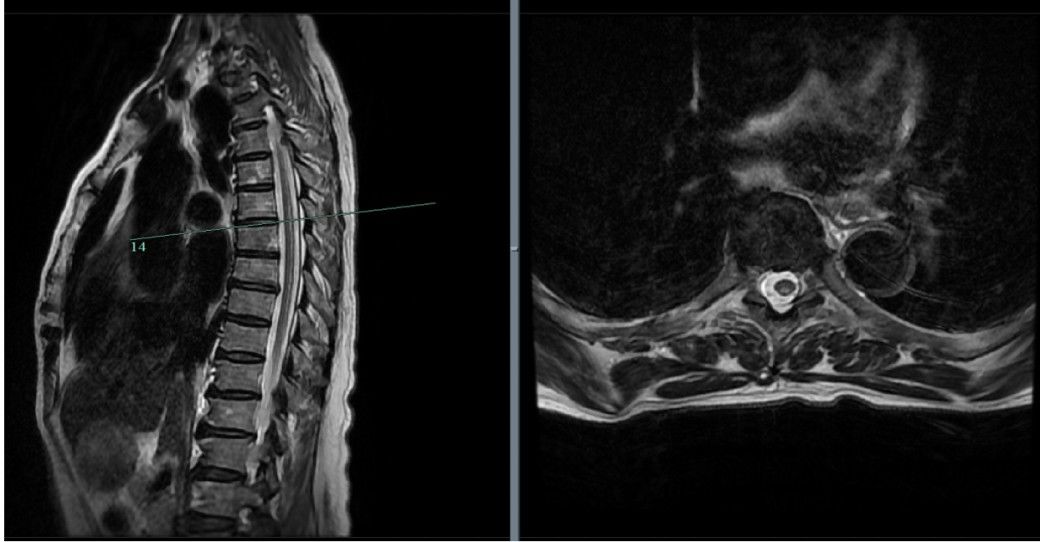

檢查顯示神經(jīng)受損病因找到了?神經(jīng)內(nèi)科醫(yī)生接診了黃阿姨,“她當時過來的時候情況不太好,坐在輪椅上,全身乏力,精神欠佳。”醫(yī)生給她開了胸椎MR檢查,結(jié)果顯示,黃阿姨上下肢周圍神經(jīng)、中樞神經(jīng)都受到了嚴重損傷。

文章插圖

同時,經(jīng)過血液檢測,黃阿姨的血紅蛋白指標只有70g/L,符合大細胞貧血。不僅如此,黃阿姨體內(nèi)的維生素B12水平也嚴重低于正常水平。就像將拼圖正確拼插后,神經(jīng)內(nèi)科專家團隊為黃姨的癥狀找到了病因:維生素B12缺乏導致的脊髓亞急性聯(lián)合變性(SCD)、周圍神經(jīng)病變和大細胞貧血。